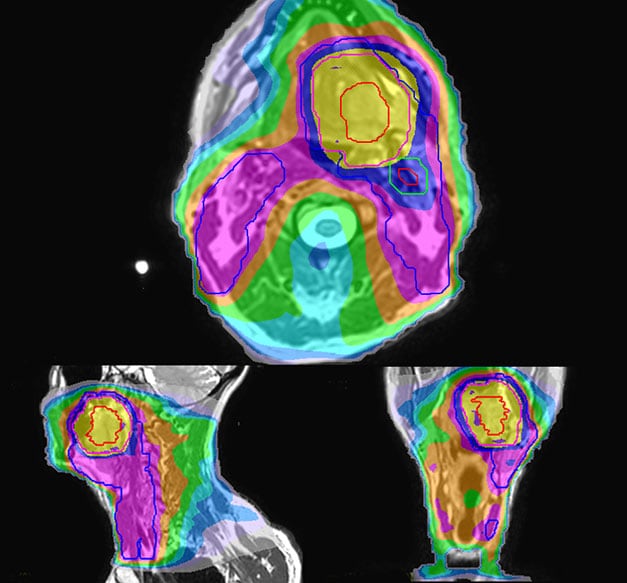

Prostate MR-only radiotherapy planning with use of rectal spacer

Hôpital de La Tour uses an implanted rectal spacer (SpaceOAR®, Boston Scientific) for patients receiving prostate radiotherapy to provide space between the rectum and prostate. 3D T2W TSE MRI provides excellent rectal spacer visualization and is used for OAR and target contouring. The dose plan is calculated on the MRCAT dataset.

Simulation imaging

Tranversal 3D T2W TSE with Compressed SENSE, acquired on Ingenia MR-RT 1.5T (left).

On-console generated MRCAT (right).

MR-based contouring and planning

MRCAT is primary image dataset for dose calculation (left).

3D T2W TSE MRI with 36 cm Field-of-View is used for delineation of prostate and organs at risk (right).